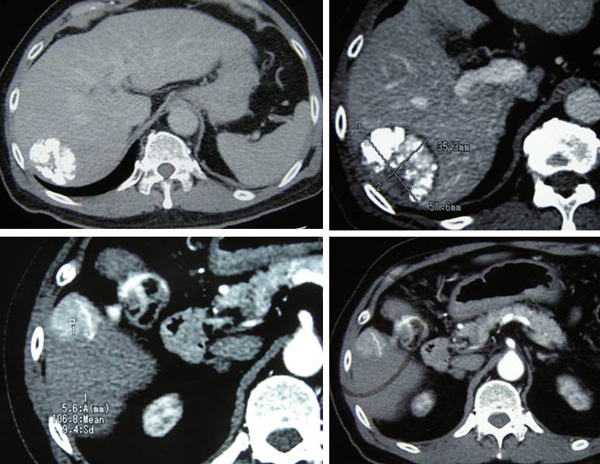

CT scan on 2 June 2010 showed a solitary mass in segments 6 and 7 in the right lobe of his liver, It  measures 7.8 x 6.5 x 8.4 cm. This is compatible with a hepatoma. There is no involvement of the hepatic or portal veins. There is no definite extension beyond the liver capsule. No enlarge lymph nodes were seen in the para-aortic or portahepatis region.

After two cycles of TACE, CT scan on 5 August 2010 showed the tumour has shrunk. The entire mass now measures 6.2 x 4.5 x 5.5 cm. The response was good with no evidence of metastasis.

CT scan on 6 October 2010 showed the tumour was significantly smaller in size, 4.7 x 5.4 x 4.6 cm. There was no evidence of recurrent or new lesions in the rest of the liver. No evidence of pulmonary metastataic deposits and no enlarged mediastinal or lymph nodes.

On 6 April 2011, a CT scan was performed. The previously treated mass in the right lobe of his liver measures approximately 3.5 x 5.1 x 4.8 cm in size. There is no associated hypervascularity seen with this mass. However, there is a new lesion in segment 5 of the right lobe of his liver. It is 3.1 x 2.3 x 3.6 in size.  This mass was not present on the previous scan of October 2010 and is suspicious of recurrent disease.

TD came to a private hospital in Penang and underwent a CT scan of his brain, neck, thorax, abdomen and pelvis on 12 August 2011. The results showed:

1. There is a 5.1 x 4.2 x 4.8 cm mass in segment 6 of the liver.

2. There is a 2.7 x 2.8 x 3.3 cm enhancing lesion in segment 5 of the liver.

3. There is an ill-defined enhancing lesion measuring about 2.3 cm in segment 8 of the liver.

4. There is a 2.5 x 2 x 2.1 cm mass just inferior to the right adrenal gland. Metastasis?

5. There is a 1.9 x 1.6 x 2.5 cm mass just inferior to the left adrenal gland. Metastasis?

6. There is a lytic lesion in the vertebral body of T12. Fracture of the superior endplate of T12 is noted. This probably represents a bony metastasis.